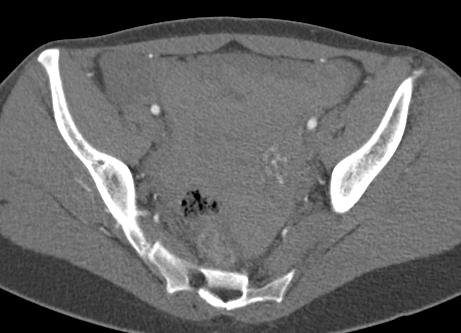

előzmény: 3 hete otthonában 6 hetes spontán vetélése zajlott. Beavatkozást nem igényelt. Tegnap délután intermittáló jellegű éles alhasi fájdalma kezdődött, hányinger kíséretében.

műtéti leírás: A hasüregben részben alvadékos vér található. A kismedencében az uterus egyenletesen megnagyobbodott, anteflexioban helyezkedik el. A vért szívóval részben eltávolítjuk ekkor észleljük, hogy a bal oldali kürtben középen kb 2 cm átmérőjű extauterin graviditás látható.